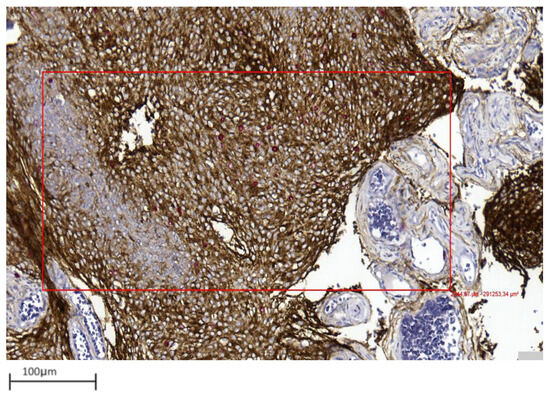

- Improved discrimination of neoplastic versus non-neoplastic cells: Unlike single-slice Ki-67 immunostaining (Figure 1), dIHC detects both markers on the same section, allowing precise differentiation between proliferating meningothelial tumour cells and components of the non-neoplastic microenvironment. EMA highlights the cytoplasm of meningothelial cells in brown, while Ki-67 marks proliferating nuclei in red. Only double-positive (EMA+/Ki-67+) cells are included in the PI count (Figure 2), whereas Ki-67-positive but EMA-negative elements (e.g., macrophages, lymphocytes, endothelial cells) are excluded (Figure 3).

Figure 1. Example of a single-slice Ki-67 staining in a grade 1 meningioma (case 1). Brown-stained nuclei indicate cells in the proliferative phase (10× magnification).

Figure 2. Example of double immunohistochemistry (dIHC) in a grade 1 meningioma (case 7). Meningothelial cells show brown membrane staining, while Ki-67 is visualized in red (40× magnification).

Figure 3. Only EMA/Ki67 in yellow square cells represent proliferating meningothelial cells in a grade 1 meningioma (case 7). Red-only cells in red square may correspond to microenvironmental elements, such as endothelial cells or small lymphocytes (40× magnification). - Integration with Digital Pathology: Digital slide scanning enables high-resolution image acquisition, allowing users to measure the selected fields (Figure 4), perform accurate cell counting (Figure 5), and virtually store or share annotated images. Distinct 1 mm2 areas were selected, and 100 neoplastic cells were counted in four “hot spots.” Digital magnification and markup tools allowed better discrimination of neoplastic cells from surrounding macrophages, vessels, and lymphocytes, ensuring higher accuracy and reproducibility (Figure 5). Two representative examples illustrating the differences in PI evaluation between single-slice Ki-67 staining and dIHC/DP are presented in Figure 6.

Figure 4. Representative image showing area selection performed with a digital tool in a grade 1 meningioma (case 17) (10× magnification).

Figure 5. The digital tool selected the area (blue box) and initiated the count of proliferating neoplastic meningothelial cells (yellow) and proliferating microenvironmental elements (red) in a grade 1 meningioma (case 17) (10× magnification).